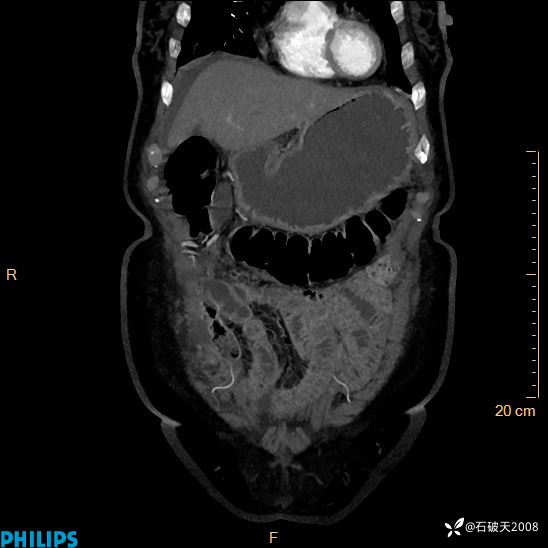

静脉期